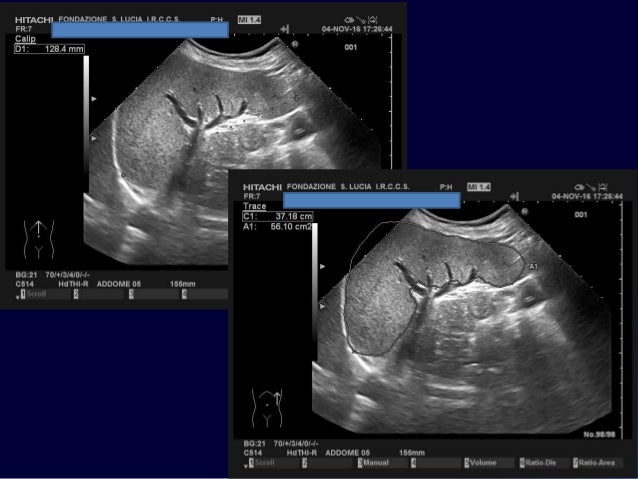

La milza ha la forma di un ovoide appiattito, con il maggior asse orientato obliquamente, dall’alto in basso, da dietro in avanti e dall’interno all’esterno;. La milza è un organo interno, delle dimensioni di un pugno, che si trova nell'addome umano Le funzioni della milza come parte del sistema immunitario e contribuisce alla produzione e stoccaggio di globuli come parte del sistema circolatorio Anche se la milza è un organo importante, ma non è essenziale per la sopravvivenza umana. Ecografia dell'addome superiore tecnica di misurazione delle dimensioni della milza normale, nel caso in esame.

Le dimensioni di una milza normale e sana possono variare considerevolmente da persona a persona Anche il tuo sesso e la tua altezza possono influenzare le sue dimensioni In generale, una milza adulta è lunga circa 5 pollici, larga 3 pollici, spessa 1,5 pollici e pesa circa 6 once. Ecografia dell'addome superiore tecnica di misurazione delle dimensioni della milza normale, nel caso in esame. Oltre alle dimensioni della milza, altri parametri devono essere presi in considerazione per la valutazione dei rischi connessi alla procedura Infatti, il tipo di patologia ematologica può giocare un ruolo fondamentale Inoltre, altri parametri relativi allo spazio di lavoro addominale sono da considerare, come l'habitus corporeo, l'indice di.

Fra le più importanti si ricordano quella emocateretica (distruzione dei globuli rossi non funzionali o deteriorati), quella immunologica, quella emopoietica e quella di separazione delle cellule ematiche e del plasma. Ecografia dell'addome superiore tecnica di misurazione delle dimensioni della milza normale, nel caso in esame. Pesa da 180 a 250 g ma questo valore, insieme alle dimensioni, varia in funzione della quantità di sangue che l.